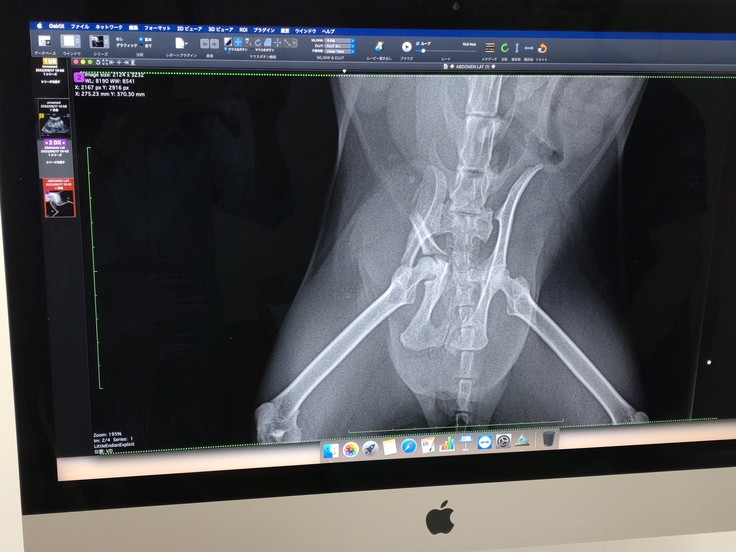

2022/9/18 検査結果と面会を兼ねて病院へ。そこでわかったのが左骨盤骨折と右骨盤のズレとの事でした。点滴を受けて300㌘増え、ご飯とちゅ~るを自力で食べていると先生が嬉しそうに教えてくれました。

2022/9/23 骨折を放置してしまうと、折れたままです固まってしまうため、早めの処置が必要な為、手術していただきました。

左の骨は3箇所以上にに折れているので、薄い板のようなもので補強し固定していただきました。

複雑骨折しているようで、ネコちゃんの薄い骨では固定しきれないところもあるようですが、あまり影響なく過ごせるそうです。

右はズレているのを元の位置にネジで固定していただきました。